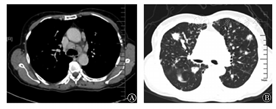

A:纵隔窗,两侧肺门、纵隔可见肿大淋巴结,最大者短径约1.5 cm;B:肺窗

不伴BO的胸部受累MCD组共7例(23.3%),3例(42.9%)为透明血管型,4例(57.1)为浆细胞型(图3)。其中,男性3例,女性4例,年龄35~70岁,平均年龄49.29岁,明显大于前两组[分别为(27.20±3.76)岁及(37.17±2.87)岁,P值分别为0.005及0.034]。5例(71.4%)患者有胸部症状:主要症状为咳嗽(4例,占57.1%),1例伴气促,1例表现为胸痛。其余1例因发现颈部肿物就诊,1例为体检发现。2例透明血管型患者血常规正常,1例存在轻度贫血(HGB 100 g/L)。3例透明血管型患者红细胞沉降率、血清球蛋白及血气分析均正常。4例浆细胞型患者中3例存在贫血,HGB 88.0~96.0 g/L(均值为92.7 g/L);红细胞沉降率均明显增高,为104~140 mm/1 h,均值为118.7 mm/1 h;免疫球蛋白G(IgG)均增高,为22.0~176.0 g/L,均值为75.3 g/L;2例患者血气分析正常,2例患者存在轻度低氧血症,不吸氧情况下动脉血氧分压73.1~78.8 mmHg(1 mmHg=0.133 kPa)。6例患者肺通气功能正常,1例存在轻度限制性通气功能障碍。3例透明血管型患者为肺门和(或)纵隔淋巴结受累伴全身其他淋巴结[颈部、锁骨上、腋窝、腹部和(或)腹股沟]受累,4例浆细胞型患者均有肺实质受累,伴肺门和(或)纵隔淋巴结和(或)全身其他淋巴结[颈部、锁骨上、腋窝、腹部和(或)腹股沟]受累。CT显示淋巴结长径(3.10±0.93)cm,明显小于前两组[分别为(9.87±1.62)cm及(5.41±0.50)cm,P值分别为<0.001及0.036];淋巴结短径(1.83±0.51)cm,明显小于前两组[分别为(4.73±1.63)cm及(3.62±0.26)cm,P值分别为0.006及0.011]。淋巴结平扫CT值为30~49 HU,均值为39 HU,5例(71.4%)密度均匀,2例密度不匀,强化后CT值为62~92 HU,均值为79 HU(图4A)。4例肺实质受累患者表现为双肺弥漫性病变,分别表现为:①双肺间质性肺炎,双肺小叶间隔增厚,可见磨玻璃状、斑片状模糊影;②两肺弥漫分布斑点、斑片状模糊影,部分可见树芽征,部分病灶为结节状(0.2~0.3 cm),伴点状小钙化,双上肺为著,其内可见支气管气相;③双肺小叶间隔增厚,两肺可见多发大小不等磨玻璃结节影(病变最大者直径为0.84 cm),沿肺纹理分布,边缘稍模糊,可见毛刺,病变可累及斜裂胸膜;④两肺可见多发斑片状、团片状实变影(病变最大者直径为2.5 cm)及磨玻璃密度影,以实变影为主,可见支气管气相,病变可累及斜裂胸膜(图4B)。2例浆细胞型患者脾脏肿大,2例患者行颈部淋巴结活检明确诊断,2例患者行纵隔肿物切除术明确诊断(其中1例同时行锁骨上淋巴结活检),其余3例有肺实质受累的患者均行肺楔形切除术,其中1例同时行纵隔淋巴结活检。明确诊断后分别予化疗、糖皮质激素、沙利度胺、利妥昔单抗治疗,合并间质性肺炎患者同时加用吡非尼酮治疗,间质性病变有所吸收。最长随诊时间为10年,病变进展缓慢。30例胸部受累CD患者中5例患者行PET-CT检查,肿大淋巴结糖代谢增高,最大标准摄取值为3.1~5.1,均值为3.9。